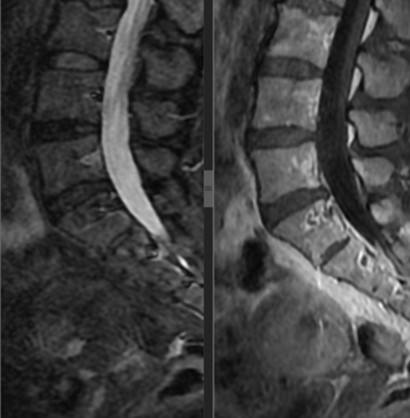

Figura 5. Tras ocho ciclos de quimioterapia, los estudios de imagen de control evidenciaron una respuesta radiológica completa.

La paciente cumplió con ocho ciclos de quimioterapia, observando respuesta radiológica completa en sus estudios de imagen control (Fig 6 y 7.).